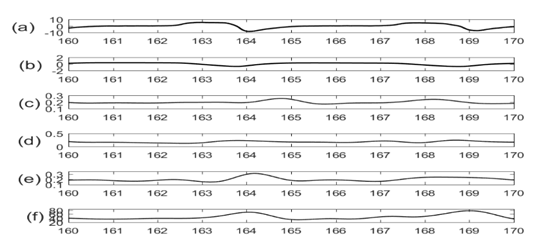

Figure 2 shows the physiological signals with their upper and lower envelopes suggesting that baseline and amplitudes of these signals noticeably vary with respiration.

Figure 2 Traces of different physiological signals (a) Lung volume (b) SCG-craniocaudal with upper & lower envelope (c) SCG-lateral with upper & lower envelope (d) SCG-dorsoventral with upper & lower envelope. SCG envelopes suggest that the baseline wondering, and amplitude modulation of these signals have a period similar to respiration.

Figures 3 & 4 show the baseline wondering and amplitude modulation of SCG signals plotted along with lung volume changes that are calculated from respiratory flow measurements.

Figure 3 Traces of (a) Lung volume changes; (b) SCG-craniocaudal baseline; (c) SCG-lateral baseline; (d) SCG-dorsoventral baseline signals.

Figure 4 Traces of (a) Lung volume changes; (b) Amplitude modulation of SCG-craniocaudal; (c)Amplitude modulation of SCG-lateral; (d) Amplitude modulation of SCG-dorsoventral.